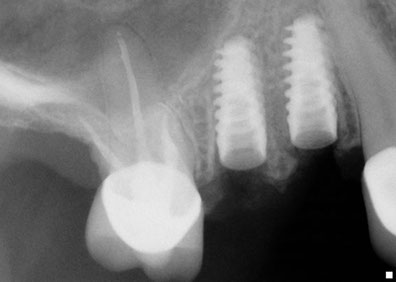

A quick and safe solution to facilitate the installation of dental implantsIn 1960, it was Philip Boyne who first used the Caldwell-Luc procedure to correct the lack of maxillomandibular space by raising the sinus membrane in the area of the molars and premolars and placing a graft composed of particulate or autogenous corticocancellous bone (originating from the patient) at the base of the to fill the bone cavity. With the arrival of titanium root implants, it was discovered that many people’s upper maxillary bones were inadequate in height and bone width, requiring a bone graft in the maxillary sinus to make them suitable recipients of for dental implants. A sinus lift is a surgical procedure that is necessary when there is insufficient bone, during which bone is added in between the upper maxilla and the maxillary sinuses, which are an annex to the nasal passages. Found on both sides of the nose, the shape and size the maxillary sinus varies in each person and with the passage of time it becomes larger (inappropriate for dental implants).

This technique is used in dentoalveolar surgery, oncology and traumatology, with the objective being to fix a craniofacial bone defect, etc. A sinus lift is a safe solution through which it is possible the implantation of osseointegrated dental implants, resulting in better looking and functioning teeth.

Who is a candidate for this technique?This technique is recommended in cases where it is impossible to place dental implants with the proper length required in the posterior upper jaw bone. In this area there is usually a type III or IV bone quality and because of this, it is necessary to use an implant with a minimum length of 10mm and the largest possible diameter.

The elevation of the maxillary sinus is one of the most versatile surgical implant techniques to allow the placement of dental implants.